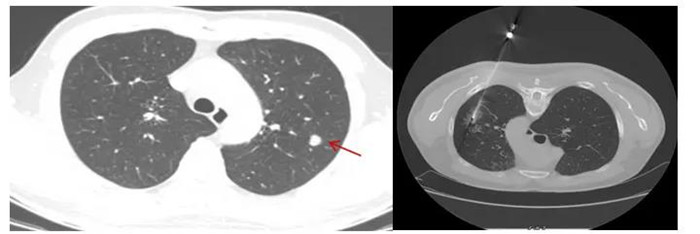

CT引導(dǎo)下肺穿刺活檢,8毫米肺結(jié)節(jié)排除肺癌可能

黃先生肺結(jié)節(jié)的性質(zhì)變得難以確定,經(jīng)評(píng)估,金旭如帶領(lǐng)呼吸介入團(tuán)隊(duì)給黃先生行肺穿刺活檢。

“通過CT掃描測(cè)量,確定穿刺進(jìn)針點(diǎn)、方向、距離,使用肺穿刺針經(jīng)胸壁穿刺到肺結(jié)節(jié)部位,進(jìn)行3~4次切割取材,獲取組織送檢驗(yàn)及病理切片?!睉c幸的是,穿刺結(jié)果顯示,黃先生的肺結(jié)節(jié)為:肺隱球菌病。

CT定位下經(jīng)皮肺穿刺活檢